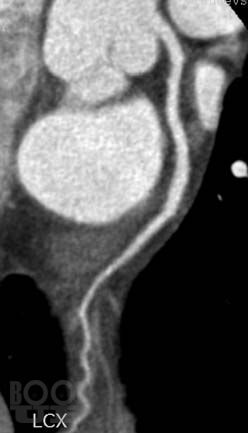

Достоинствами метода МСКТ-КГ являются неинвазивность и возможность оценить не только просвет коронарной артерии, проходимость аортокоронарных шунтов и стентов, но и состояние стенки сосуда, структуру атеросклеротической бляшки, а также возможность визуализации полостей сердца, миокарда и анатомических структур в зоне исследования.